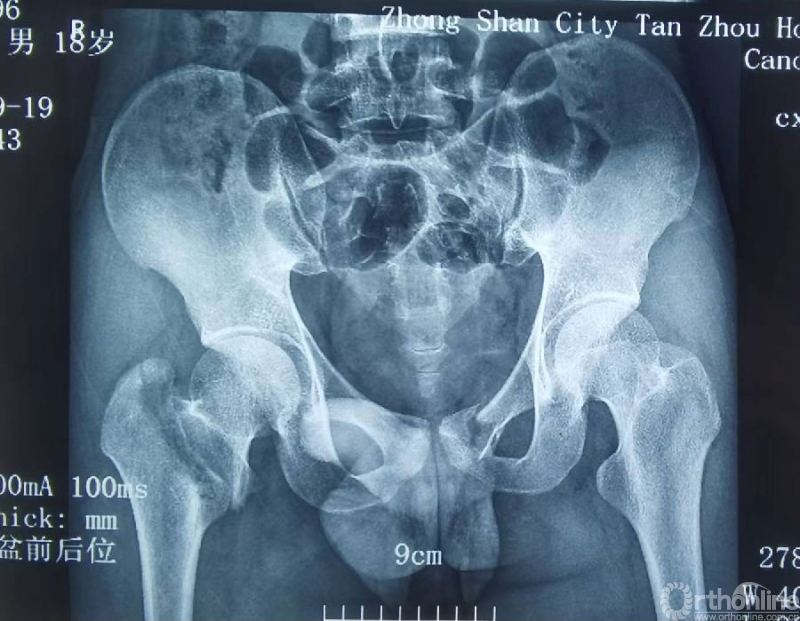

患者黄某,男性,19岁。

主诉:右髋部疼痛、功能受限10月余。

现病史:10月余前因外伤致右髋部骨折,于外省某医院行切开复位钢板内固定术,术后近1年因右侧髋关节疼痛不敢下地行走,患侧髋关节活动受限。

影像学资料

诊断:股骨颈基底部骨折(Garden III)并转子间骨折

初次治疗:切开复位锁定钢板内固定

骨折术后骨不连(2022.3)

骨折术后骨不连(2022.7.3)